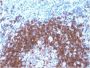

Positive Control

MCF-7 cells or Cervical carcinoma

IHC, FFPE (verified)|WB (verified)

IHC (FFPE) (verified)|WB (verified)

Higher concentration may be required for direct detection using primary antibody conjugates than for indirect detection with secondary antibody|Immunofluorescence: 1-2 ug/mL|ELISA: 2-4 ug/mL for coating order Ab without BSA|Immunohistology (formalin): 0.5-1 ug/mL|Staining of formalin-fixed tissues requires boiling tissue sections in 10 mM citrate buffer, pH 6.0, for 10-20 min followed by cooling at RT for 20 min|Flow Cytometry 0.5-1 ug/million cells/0.1 mL|Western blotting 0.5-1 ug/mL|Optimal dilution for a specific application should be determined by user